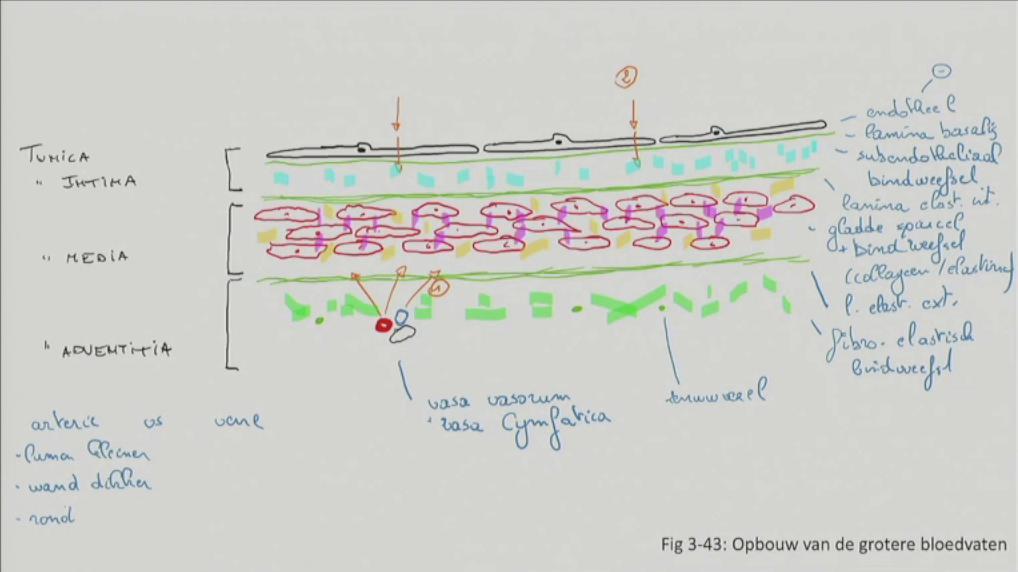

Fig 3.43: Opbouw van grotere bloedvaten

|

|

Fig 3.44: Opbouw van verschillende types arterien

A arteriool (< 500 um)

B musculaire arterie (rode kleur)

C elastische arterie (gele kleur, bv. aorta)

-

tunica intima

lamina elastica interna -

tunica media

gladde spiercellen elastinevezels

lamina elastica externa -

tunica adventitia

|